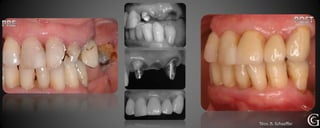

Prótesis Fija Convencional

Puentes

Los puentes son restauraciones que sirven para reemplazar piezas

perdidas, involucrando piezas vecinas. Son confeccionadas fuera

de la boca y luego adheridas o cementadas a los dientes vecinos a

a la pieza perdida.

Prótesis Fija Convencional Puentes Los puentes son restauraciones que sirven para reemplazar piezas perdidas, involucrando piezas vecinas. Son confeccionadas fuera de la boca y luego adheridas o cementadas a los dientes vecinos a a la pieza perdida.